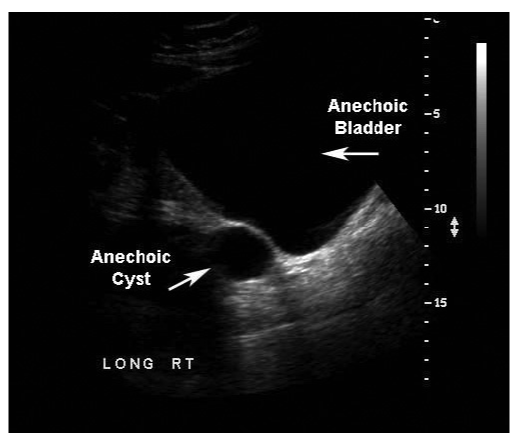

Anechoic regions in fluid-filled structures.